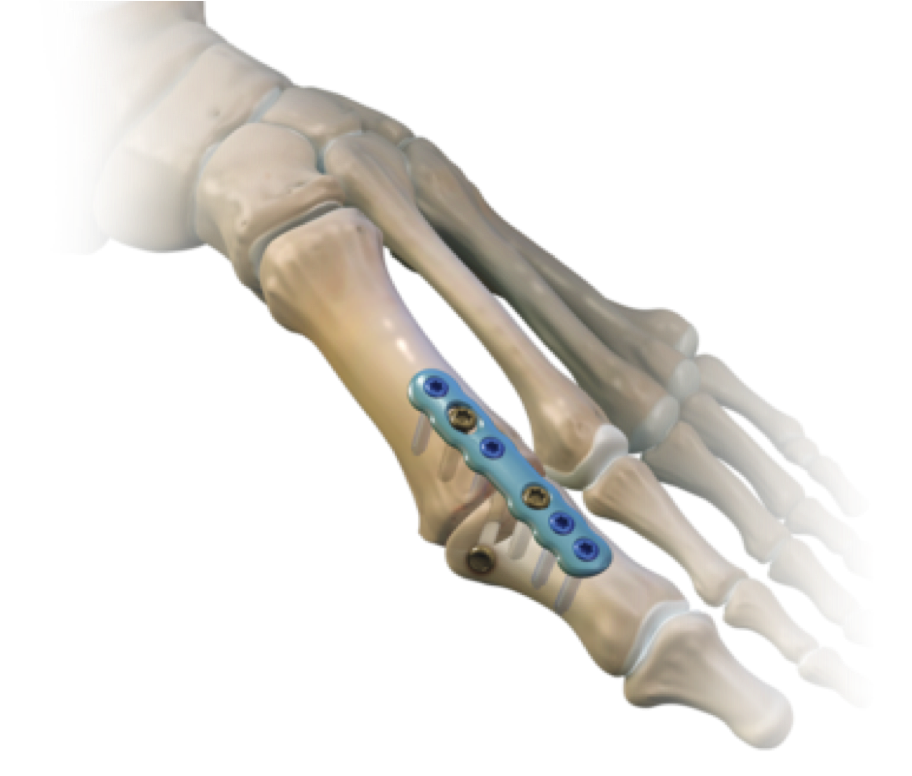

A artrodese articular, isto é, a fusão dos ossos para eliminar o movimento da articulação e consequentemente a dor, é utilizada como alternativa de tratamento definitivo. O dedo deve ser posicionado de forma a manter o conforto para deambular sem ocasionar atrito com o calçado ou o contato excessivo com o chão.